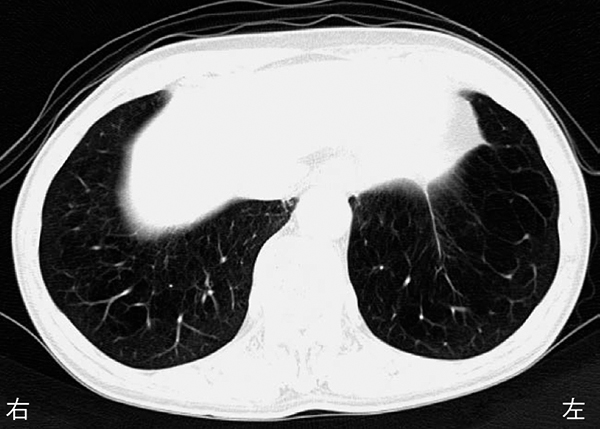

80歳の男性.胸部CTを下に示す.この患者で

- 1.肥 満

- 2.残気量の低下

- 3.一秒率の低下

- 4.気道抵抗の低下

- 5.肺コンプライアンスの低下

解答: 3